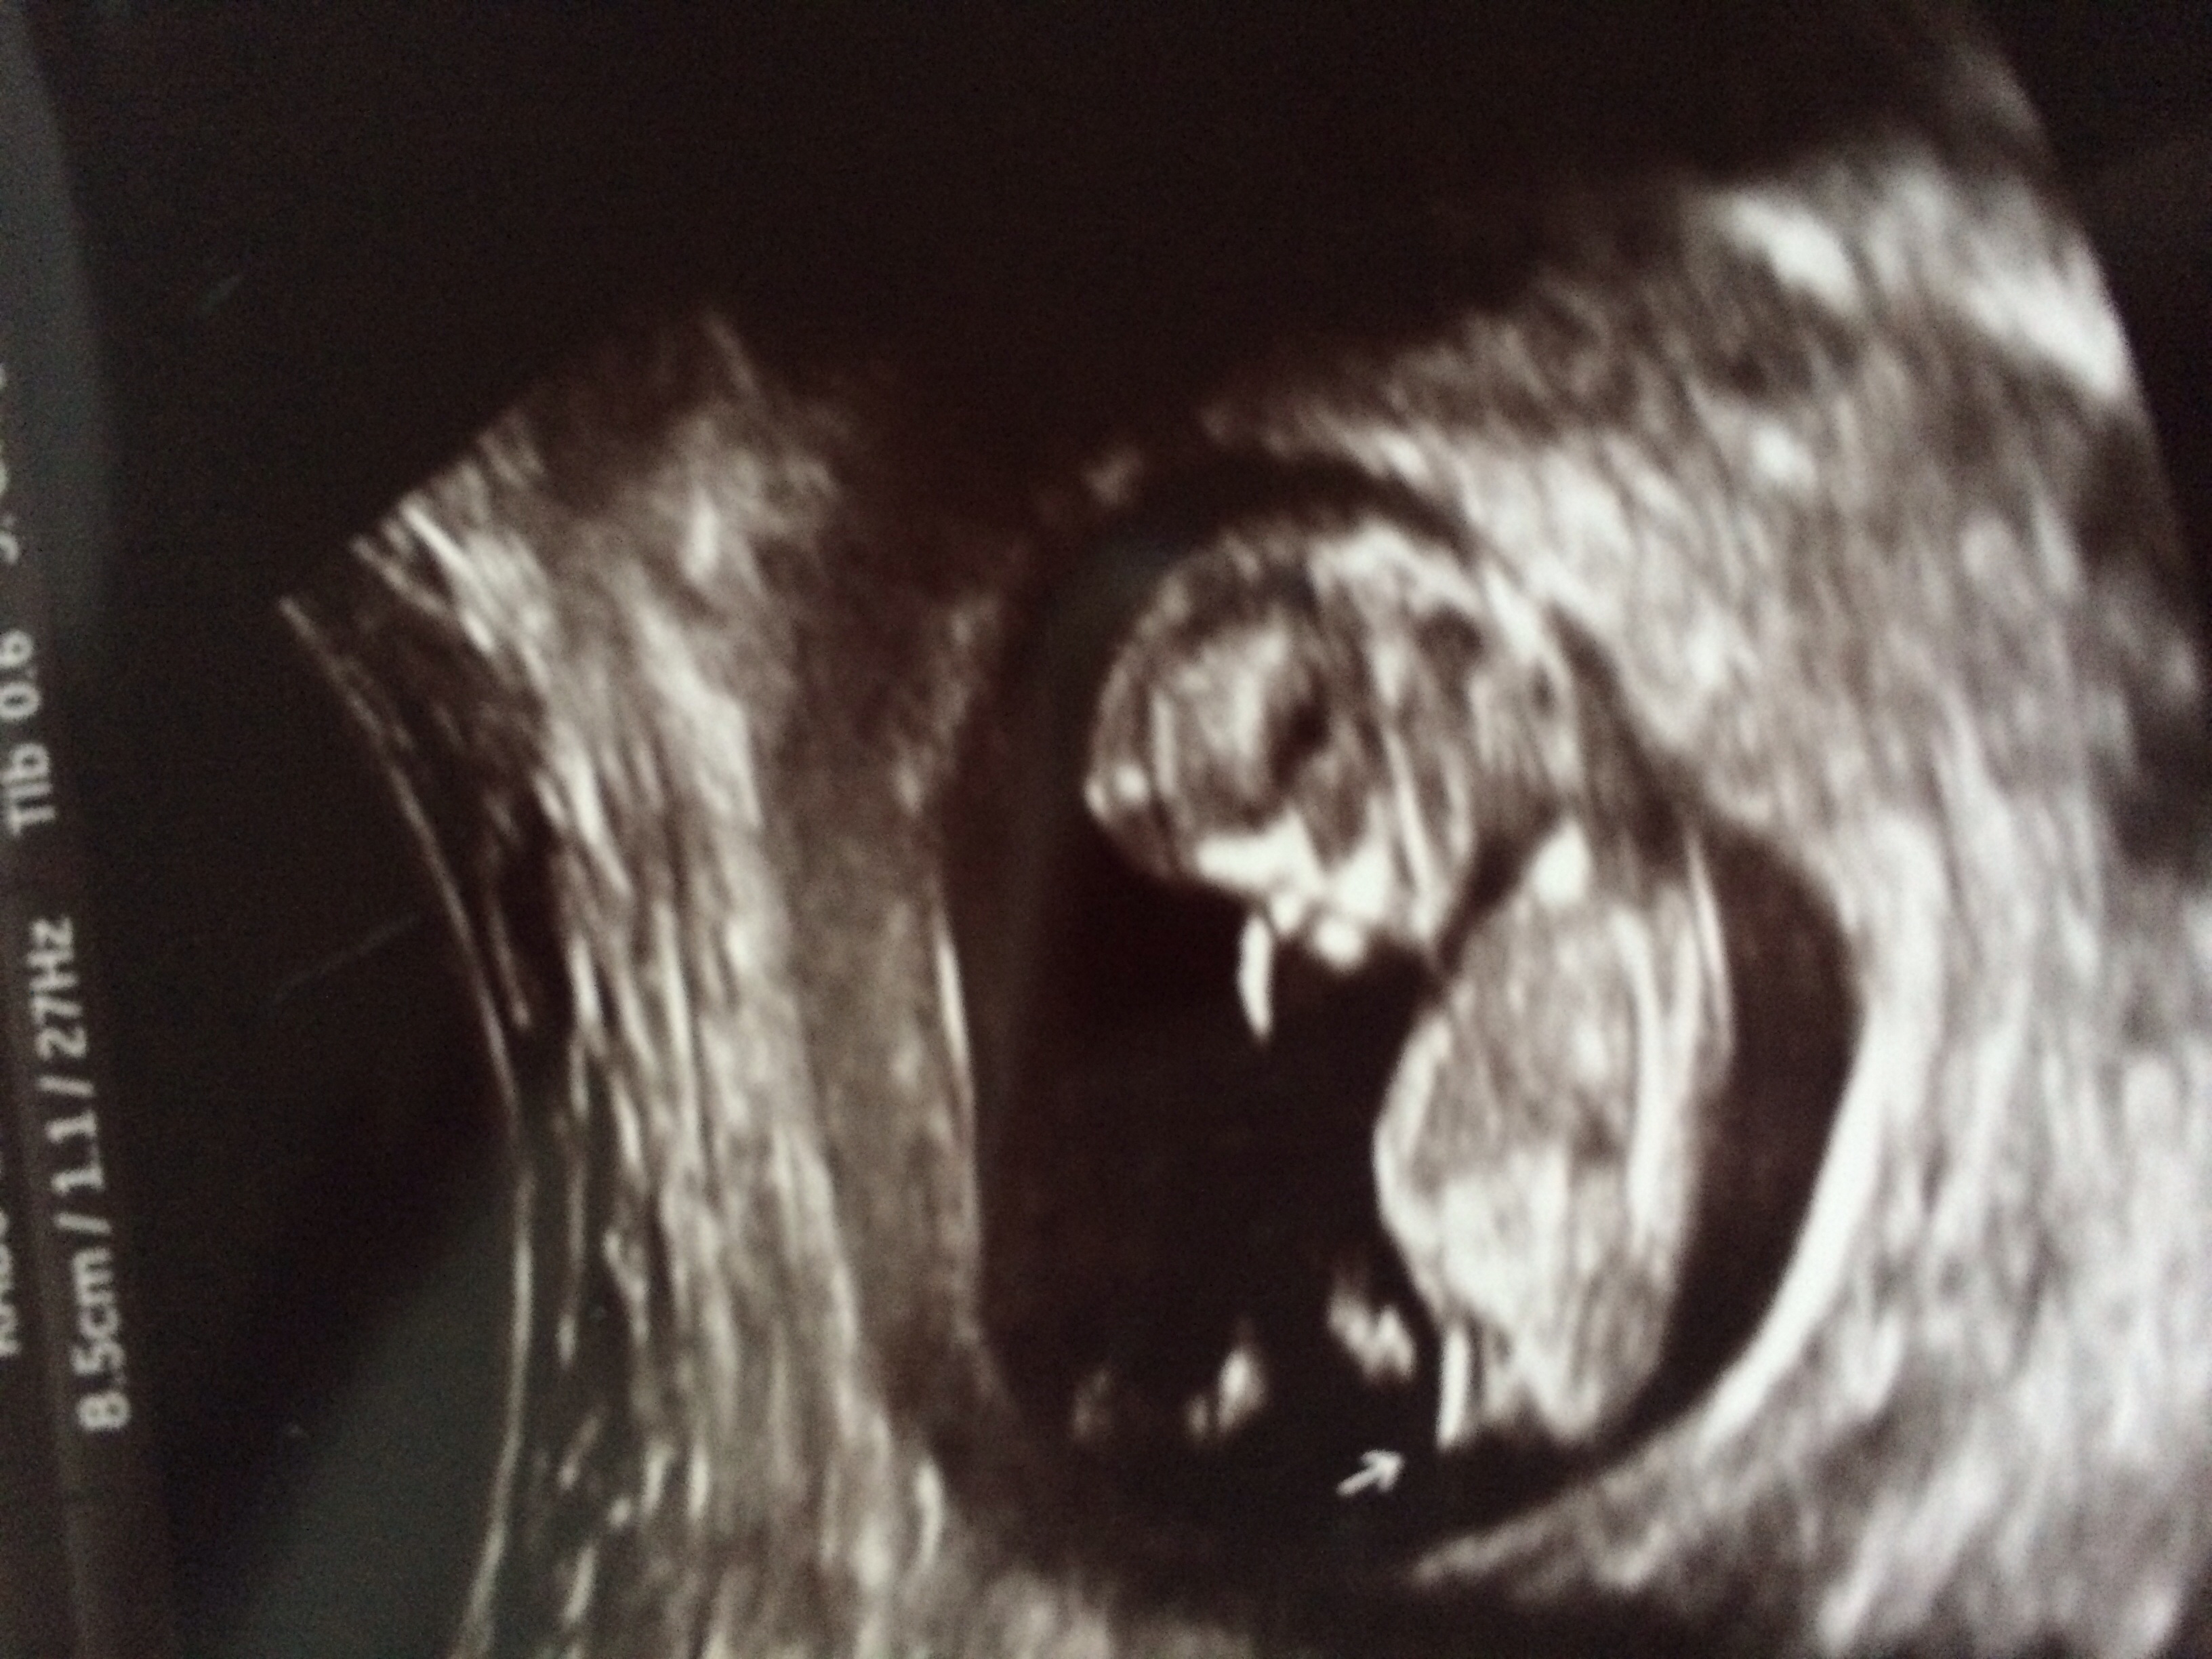

12 week nub shot guess :)

Girl